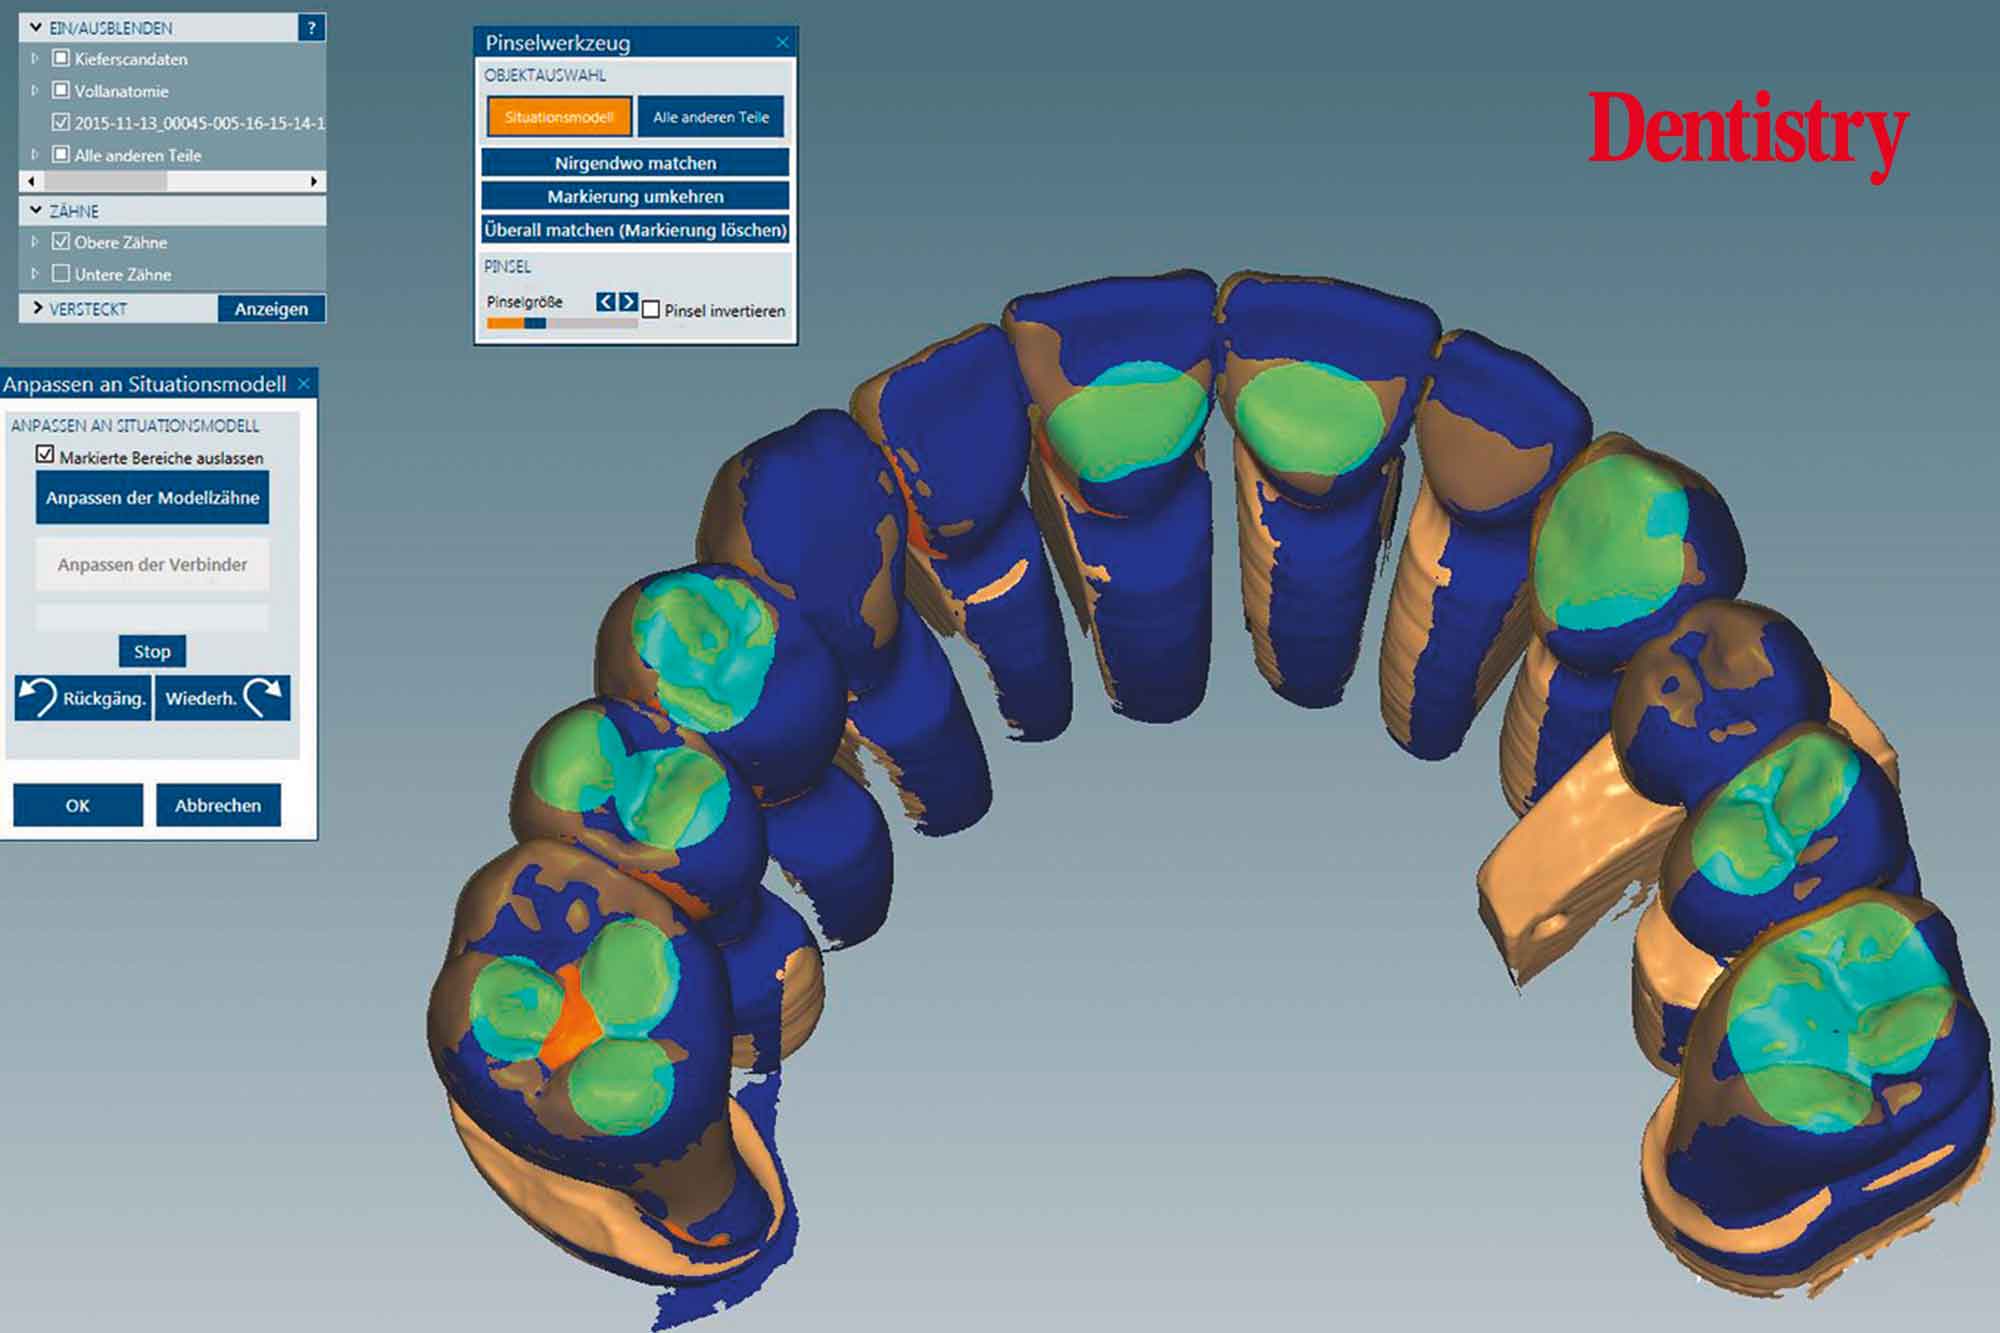

Figure 13 shows the areas that were adjusted intraorally in green and the remaining unchanged areas in blue. The plan was to fabricate Ceramill Zolid FX crowns on the maxillary teeth first. This is so subsequent corrections on the lower temporary crowns would mean that less corrections would be necessary for the final lower crowns.

Canine guidance with a light group function was created on the Ceramill Mind Wizard.